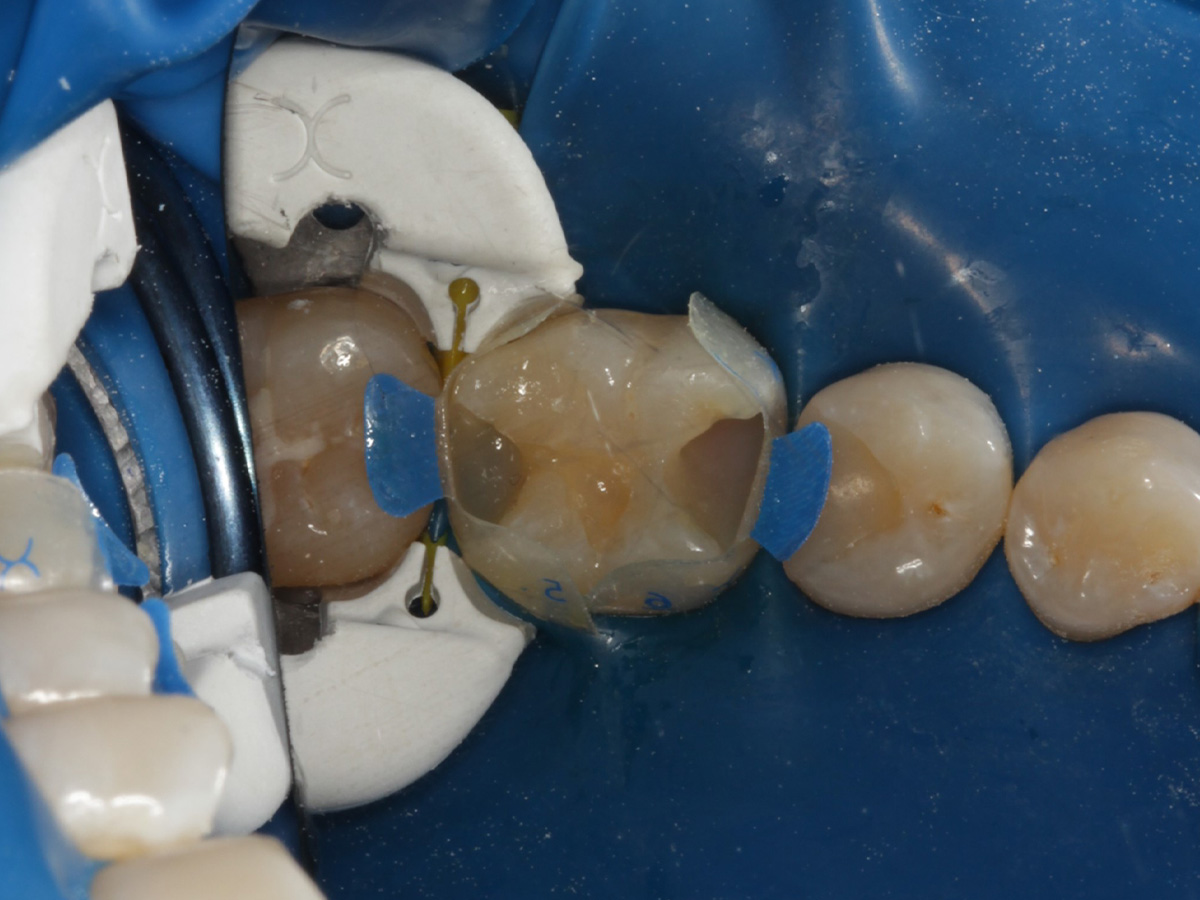

Abbildung 2

Quadrantenisolierung mit Kofferdam (x-heavy)

Abbildung 3

Schutz des Nachbarzahnes und des Kofferdams mit wiederverwandter Bioclear Biofit Matrize (gereinigt und sterilisiert); Separation zur Applikation der Matrize mit Heidemannspatel

Abbildung 4

Defektdarstellung; „Schutzmatrizen“ ideal als „Leitplanken“ bei der Zahnpräparation tief approximal bis in gesunde Zahnsubstanz

Abbildung 5

Kariesexcavation pulpennah mit Kunststoffrosenbohrer